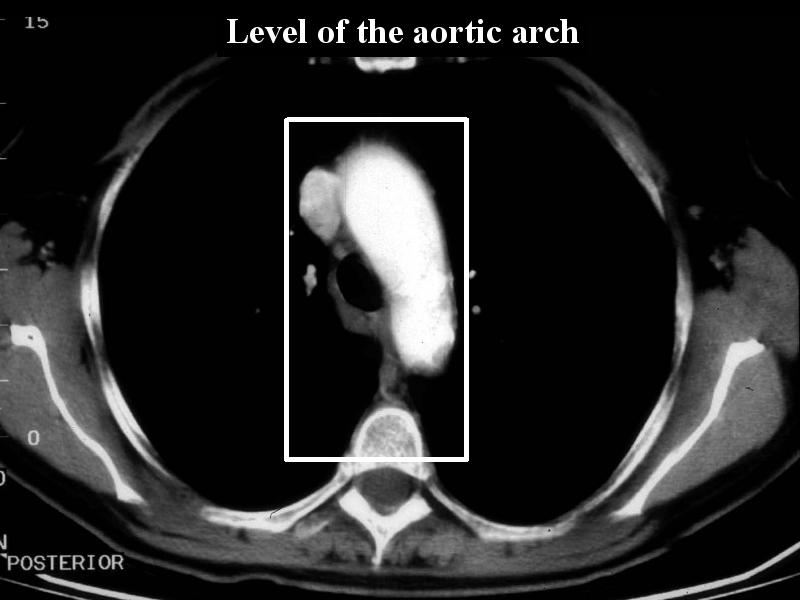

MS 156 CT NL 58